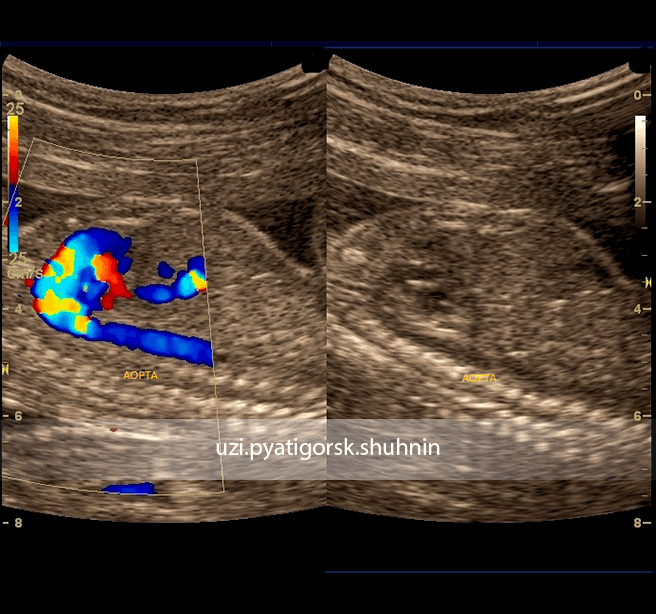

На фото из собственной практики д-ра Р. Шухнина:

УЗИ, 2-й скрининг беременности. Режим ЦДК и В-исследования. Грудная аорта плода в норме. Отчетливо визуализируется грудная аорта на всем протяжении без видимых изменений, это же подтверждено цветовой спектрографией кровотока в ней.

УЗИ, 2-й скрининг беременности. Режим ЭД. Отчетливо визуализируется участок коарктации (стрелка) дуги аорты. Установлен диагноз коарктации аорты.